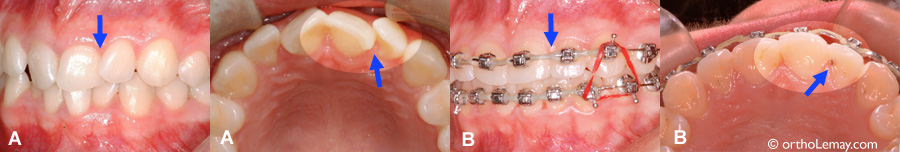

Apparition de caries entre des dents antérieures pendant l’orthodontie-2

(A) La rotation d’une centrale et latérale cache une carie sur la face interne de la latérale. (B) Après la correction des rotations, la carie est visible sur la latérale et peut être plus facilement accessible pour le dentiste afin d’être réparer.

Apparition de caries entre des dents antérieures pendant l’orthodontie-3

(A) Incisives en rotation et se chevauchement légèrement. (B) Une légère tache foncée (carie arrêtée) est visible après la correctino des rotations. (flèche)